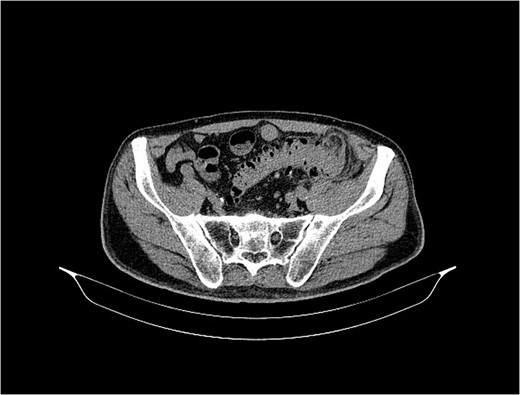

An urgent multidetector computed tomography of the abdomen and pelvis with contrast medium (Fig. 2) confirmed an abscess accumulation in the retroperitoneal space with diverticular disease of the left colon, and also in the lumbar region a large inflammatory accumulation with gas inclusions with a diameter of 120 × 70 mm, as well as spread to the iliac compartment and inflammation of the psoas muscle.

The control MDCT showed a condition after percutaneous drainage of a previously verified larger abscess collection in the iliopsoas region, where post-inflammatory inhomogeneous zones with a diameter of 25 mm were now seen, without clearly developed collections, but with a fistulous tract between the bowel and the left lumbar region (Fig. 2a and b). The patient was discharged from the hospital in good condition. Laboratory white blood cell count and inflammatory parameters were normal (WBC 9.5 × 109/L and CRP 2.7 mg/L).

MSCT of the abdomen and pelvis shows the sigmoid colon and skin communication with air accumulation in the axial plane.

MDCT scan of the abdomen and pelvis showed marked diverticulosis of the sigmoid and descending colon with dense fluid accumulation in the ileopsoas region and fistula formation in the lumbar region. Limited collections of thick fluid in the abdominal wall of the lumbar region with a diameter of 56 × 57 mm were also detected. The findings in the abdominal cavity were normal, with no presence of free fluid.